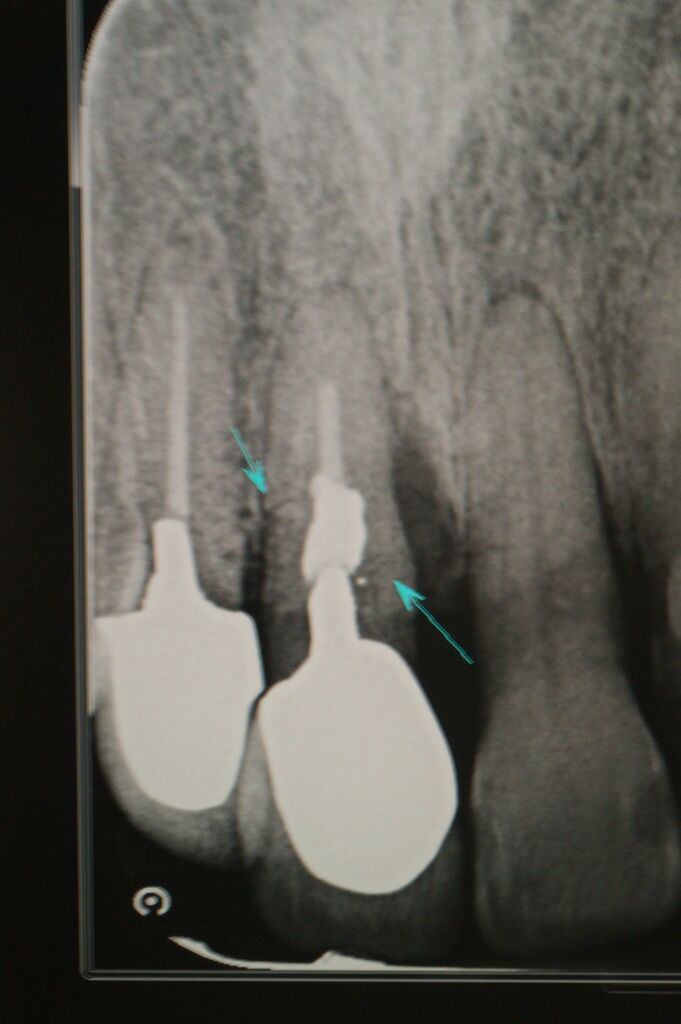

493.歯周外科(1) 2023年10月25日 15:30 この症例は歯を歯周病から救うために、やむなく外科処置を行って通常の歯石除去では取り切れない、歯周ポケット約8mmの原因になっている炎症性物質(歯垢、歯石,細菌、不良肉芽など)を廓清したものです。(大) 「歯周治療」カテゴリの最新記事 「外科処置」カテゴリの最新記事 < 前の記事次の記事 > コメント コメントフォーム 名前 コメント 評価する リセット リセット 顔 星 投稿する 情報を記憶